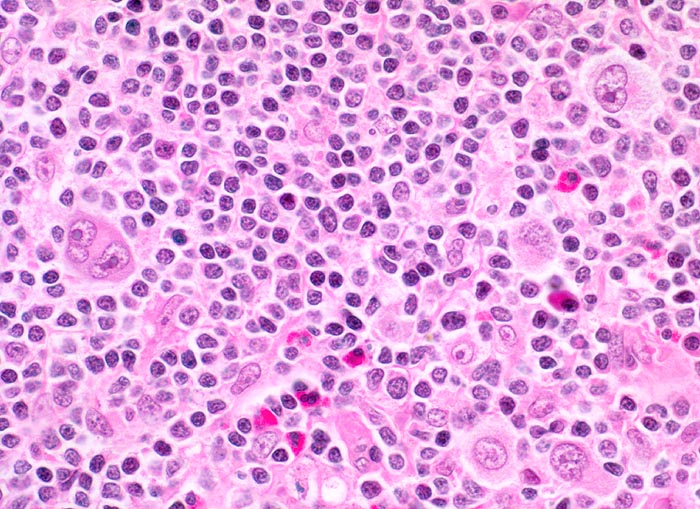

PathoPic – image database / PathoPic ID 3874 - Hodgkin-Lymphom, Mischzelltyp

Hodgkin-Lymphom, Mischzelltyp

maligner Tumor

Topographie

Lymphatische Gewebe, KM, Milz

Vergrösserte zervikale und axilläre Lymphknoten, Fieber und Nachtschweiss.

Reed-Sternberg-Zellen sind grosse mehrkernige Zellen mit spiegelbildlich angeordneten Kernen und grossen eosinophilen Nukleolen. Sie entstehen aus Hodgkin-Zellen. Im Gegensatz zur nodulären Sklerose zeigen die neoplastischen Zellen beim Mischzelltyp keinen Retraktionsartefakt des Zytoplasma.

Histologie

400